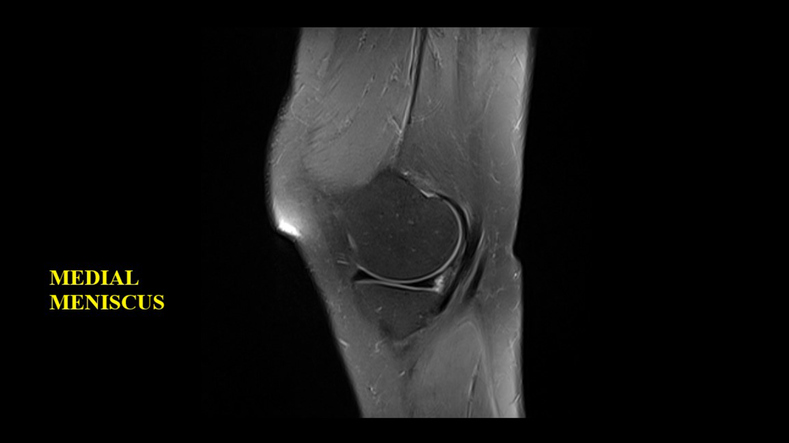

Magnetic Resonance Imaging (MRI) is a non-invasive way to get detailed pictures of your knee joint: MRI images capture various structures within the knee, including:

The method uses a powerful magnetic field and radio waves to create detailed images, allowing doctors to see what’s going on inside your knee without making a single cut.

An MRI of the knee is incredibly effective in providing detailed images of the knee joint and its surrounding structures. It helps in diagnosing a range of conditions, from sports injuries to arthritis. The clarity and detail of the images obtained from our MRI technology at Lyfe Health are second to none, offering a comprehensive look at the intricate workings of your knee.

- Meniscal tears

- Ligament injuries

- Cartilage damage

- Subtle bone fractures not visible on X-rays

MRI scans of the knee are highly accurate for diagnosing a variety of knee conditions. They are particularly effective in visualising soft tissues like ligaments, tendons, and cartilage, making them ideal for detecting tears, degeneration, or inflammation.

Can Tears in the Knee be Missed on MRI Scan?

While MRI scans are highly accurate, there’s a small chance that minor tears in the knee, especially in complex structures like the meniscus, can be missed.